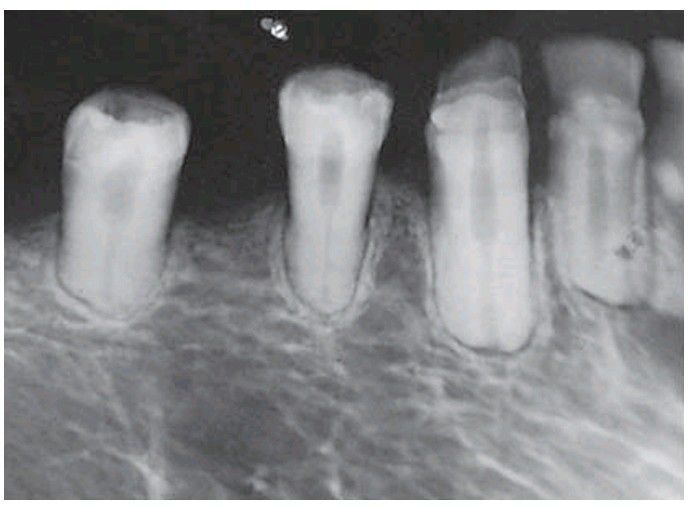

Dental anomalies in hypoparathyroidism

Teeth in childhood hypoparathyroidism with short blunt roots, open apices and large pulp chambers.